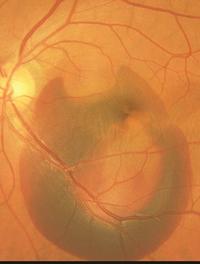

Une équipe de chercheurs a récemment publié dans JAMA Ophtalmology, les résultats à 12 mois de l’étude EVEREST II, dont l’objectif [...]

La dégénérescence maculaire liée à l’âge (DMLA) est la principale cause de malvoyance chez les plus de 50 ans en Europe et en Amérique [...]

La dégénérescence maculaire liée à l’âge est extrêmement fréquente, elle est systématiquement l’une des trois premières causes de cécité [...]